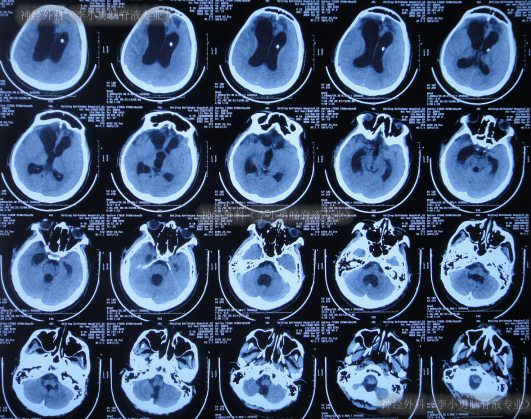

患者于2022年2月2日,不慎摔倒头部磕到地面,当时呈嗜睡状态,呕吐1次,大小便失禁,由120急送至当地县某医院,查头颅CT示右额部血肿(片子丢失),当即转至上级的河北省唐山市某医院,查头颅CT示右额部血肿、脑疝(图-1);检查期间出现昏迷、呕吐、四肢强直。

图-1:2022年2月2日头颅CT

急诊当天进行了去骨瓣减压+血肿清除术(图-2)。

图-2:2022年2月2日术后头颅CT

去骨瓣减压+血肿清除术后第2天即2022年2月3日,头颅CT示出血有增多(图-3)。

图-3:2022年2月3日头颅CT

术后3天即2022年2月4日,患者苏醒,能言语,但遗留左侧肢体不能活动,低钠血症,查头颅CT示仍有较多积血(图-4)。

图-4:2022年2月4日头颅CT